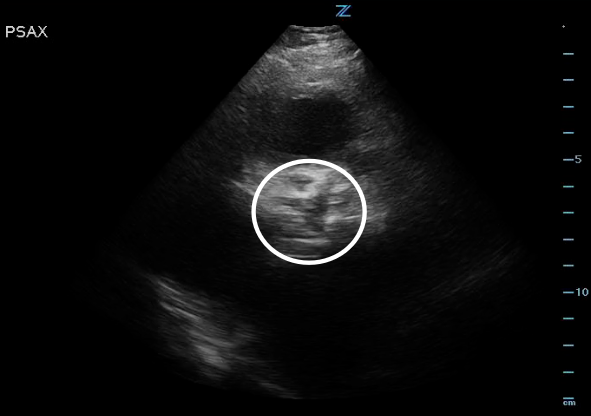

Figure 3. High PSAX (RVOT) view of the AV orifice (circled) open.